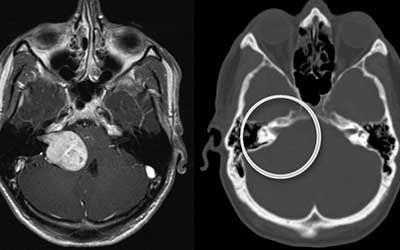

Невринома — это новообразование доброкачественной этиологии, растущее из шванновских клеток (леммоцитов), формирующих миелиновую оболочку нервных волокон. Чаще всего она поражает слуховой нерв, однако может встречаться и на любых других нервах. Её диагностируют в 10% случаев церебральных новообразований, 20% — опухолей спинномозгового канала и 50% случаев опухолей периферических нервов.

Штат нашего нейрохирургического отделения укомплектован врачами высшей категории с десятками лет опыта практической и научной работы. В их арсенале имеется мощная диагностическая и хирургическая база, позволяющая проводить комплексные исследования и добиваться наилучших результатов в лечении. Перед тем как приступить к нему, проводится комплексная диагностика, направленная определение точного места роста невриномы, её размеров, воздействия на окружающие ткани, наличие кистозных изменений. Для этого пациенту назначают:

• компьютерную томографию с контрастом;

• церебральную магнитно-резонансную томографию;